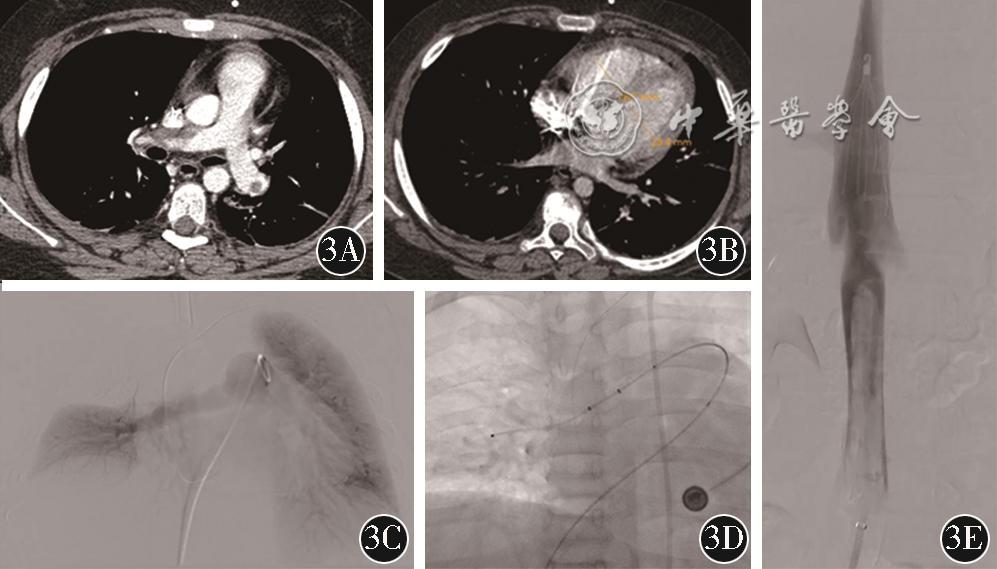

遂于2021年7月22日急诊行肺动脉导管溶栓+下腔静脉滤器置入+髂股静脉血栓清除术(图1)。DSA见右侧髂静脉血栓延续至下腔静脉,选右侧颈静脉入路;双侧肺动脉主干经猪尾导管分别予尿激酶行导管溶栓术(catheter-directed thrombolysis,CDT),左侧5万U,右侧10万U;下腔静脉肾下段放置下腔静脉滤器;分别经左侧腘静脉及右侧股静脉入路,行左侧髂-股静脉、右侧髂静脉及下腔静脉AngioJet药物机械血栓清除治疗(pharmacomechanical thrombectomy,PMT),应用尿激酶左下肢10万U,右下肢5万U;PMT后DSA造影见左侧髂静脉血流恢复,大量附壁血栓,下腔静脉滤器下方未见充盈缺损。术后予低分子肝素(8000 IU,每12 h 1次)皮下注射,左侧足背浅静脉留置针予尿激酶30万U/d,使用3 d,术后恢复良好,于2021年7月28日出院。

注:CDT为导管溶栓术;PMT为药物机械血栓清除